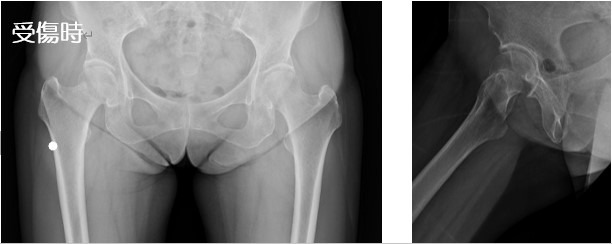

2020-07-21 手外科・外傷 ページ内リンク 髄内釘(short femoral nail) Sliding hip screw 大腿骨頚部骨折(骨接合術) 大腿骨頚部骨折(人工骨頭挿入術) 腿骨転子部骨折(髄内釘) 髄内釘(short femoral nail) Sliding hip screw 大腿骨頚部骨折(骨接合術) 大腿骨頚部骨折(人工骨頭挿入術) 腿骨転子部骨折(髄内釘) 露口 和陽 外傷・手外科部長 整形外科手外科・外傷 詳しく見る 関 謙太朗 整形外科肩関節外科手外科・外傷 詳しく見る 関連ページ 手外科・外傷 一覧へ戻る